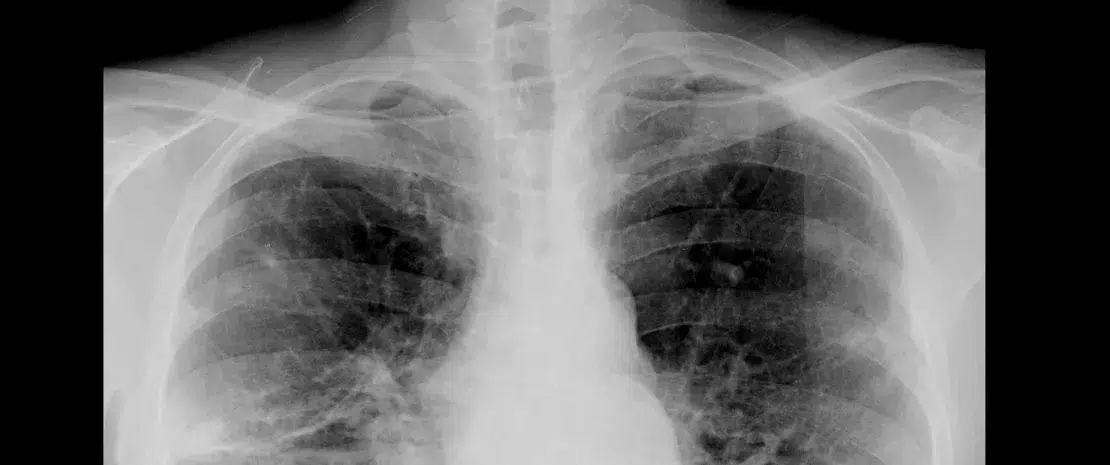

A doença pulmonar obstrutiva crónica (DPOC) afetou 3,5 milhões de pessoas em França em 2010. É responsável por mais de 100000 hospitalizações por ano por exacerbações agudas (EA)*. Estes episódios estão associados ao aumento das taxas de mortalidade a curto e médio prazo. Estudos demonstraram que os doentes com DPOC apresentam uma redução da diversidade da microbiota pulmonar, e esta disbiose tem sido citada como uma causa potencial de inflamação das vias aéreas e de uma diminuição da imunidade local.